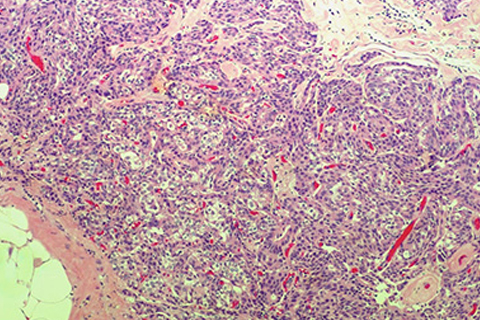

Infiltrating ductal carcinoma, breast